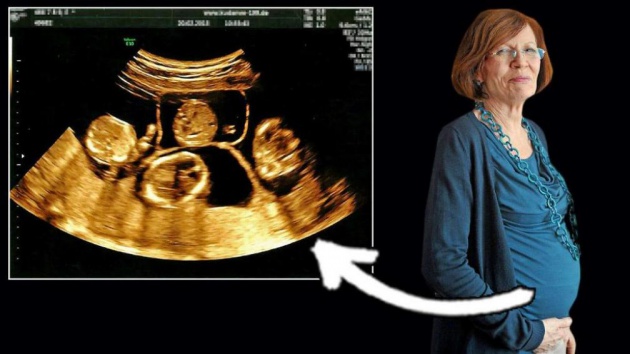

La abuela alemana de 65 años de edad, recientemente dio a luz a cuatrillizos. Ahora es la mujer de mayor edad en hacerlo.

La alemana, una madre soltera, tuvo a tres niños y una niña después de un embarazo de poco menos de 26 semanas, informó la cadena RTL.

Los bebés – cuyos nombres son Neeta, Dries, Bence y Fjonn – llegaron al mundo por cesárea y están en incubadoras para bebés prematuros, dijo la RTL.